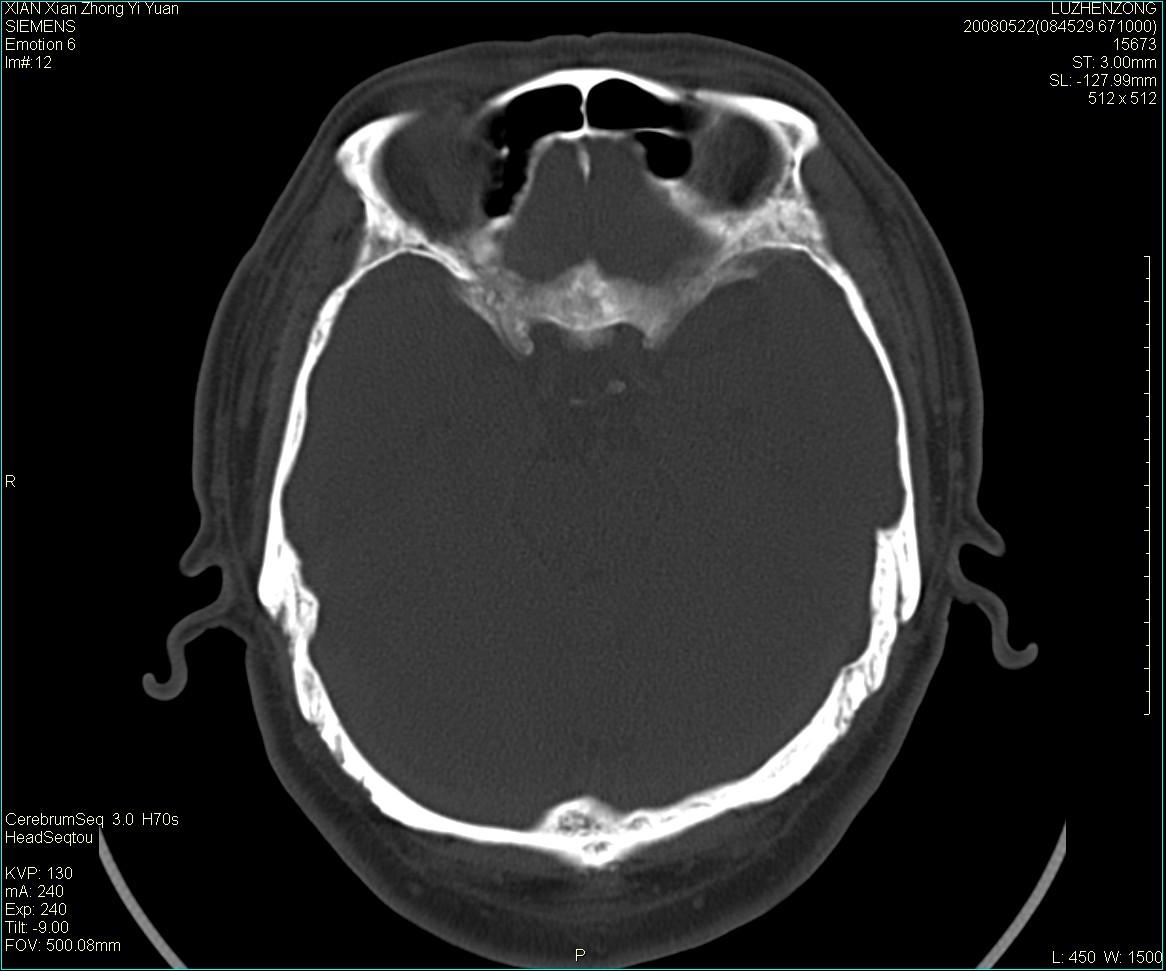

以下是引用gaoshengjiang在2008-5-28 19:06:00的发言:[br]考虑来源于蝶骨前床突区骨软骨瘤。

以下是引用卜一在2008-5-28 20:46:00的发言:[br]中颅窝“骨纤维异常增殖症”。不除外考虑来源于蝶骨前床突区“骨软骨瘤”。[br]

以下是引用liangshusheng在2008-5-28 20:13:00的发言:[br]单骨病变,考虑骨化性纤维瘤。